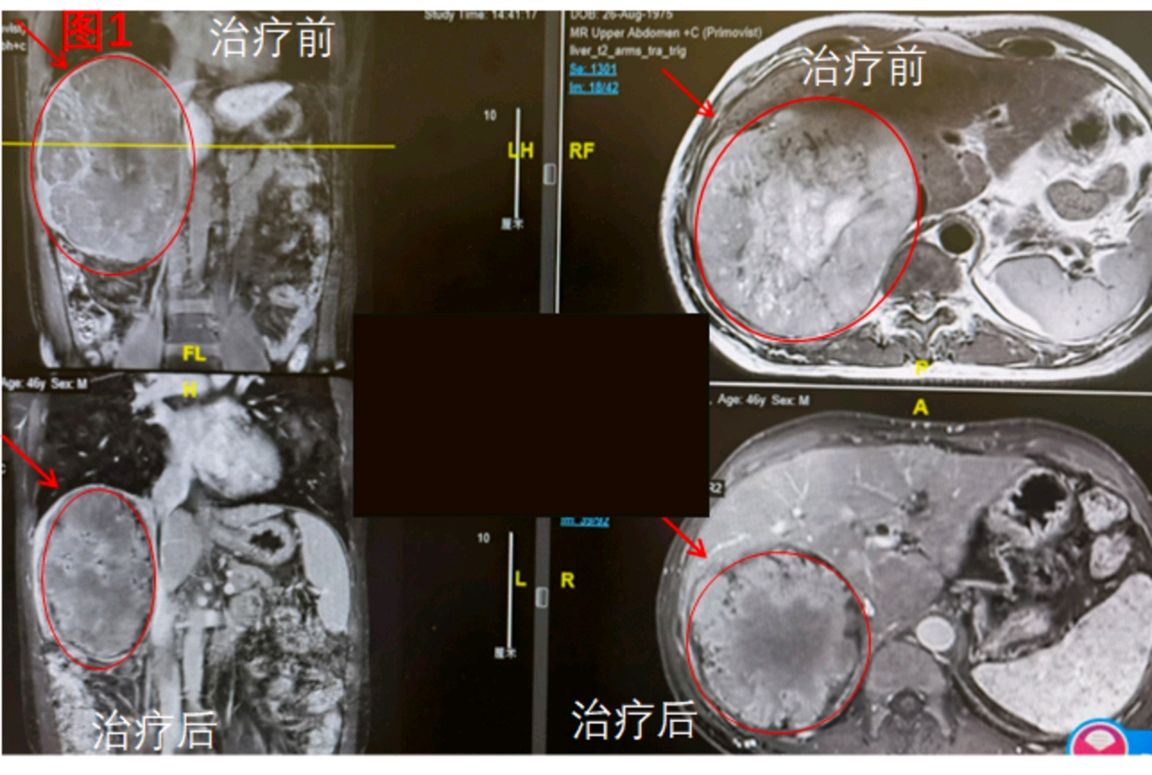

46岁男性患者,2022年2月就诊,就诊时右肝巨大肝癌194*153mm,肝右静脉及肝中静脉受侵,腹水。分期较晚,无法根治性切除。

入院后进行了5个疗程靶向免疫治疗联合肝动脉灌注化疗(HAIC)。肿瘤明显萎缩(图1)。且肿瘤标记物AFP(甲胎蛋白)从195下降至正常(图2)。2022年7月进行了积极的手术切除(右半肝切除+十二指肠修补+远端胃切除+胆肠吻合+胃肠吻合;因术中发现十二指肠球部巨大溃疡穿孔,考虑治疗副作用)。术后发生胰瘘,住院22天才康复出院。